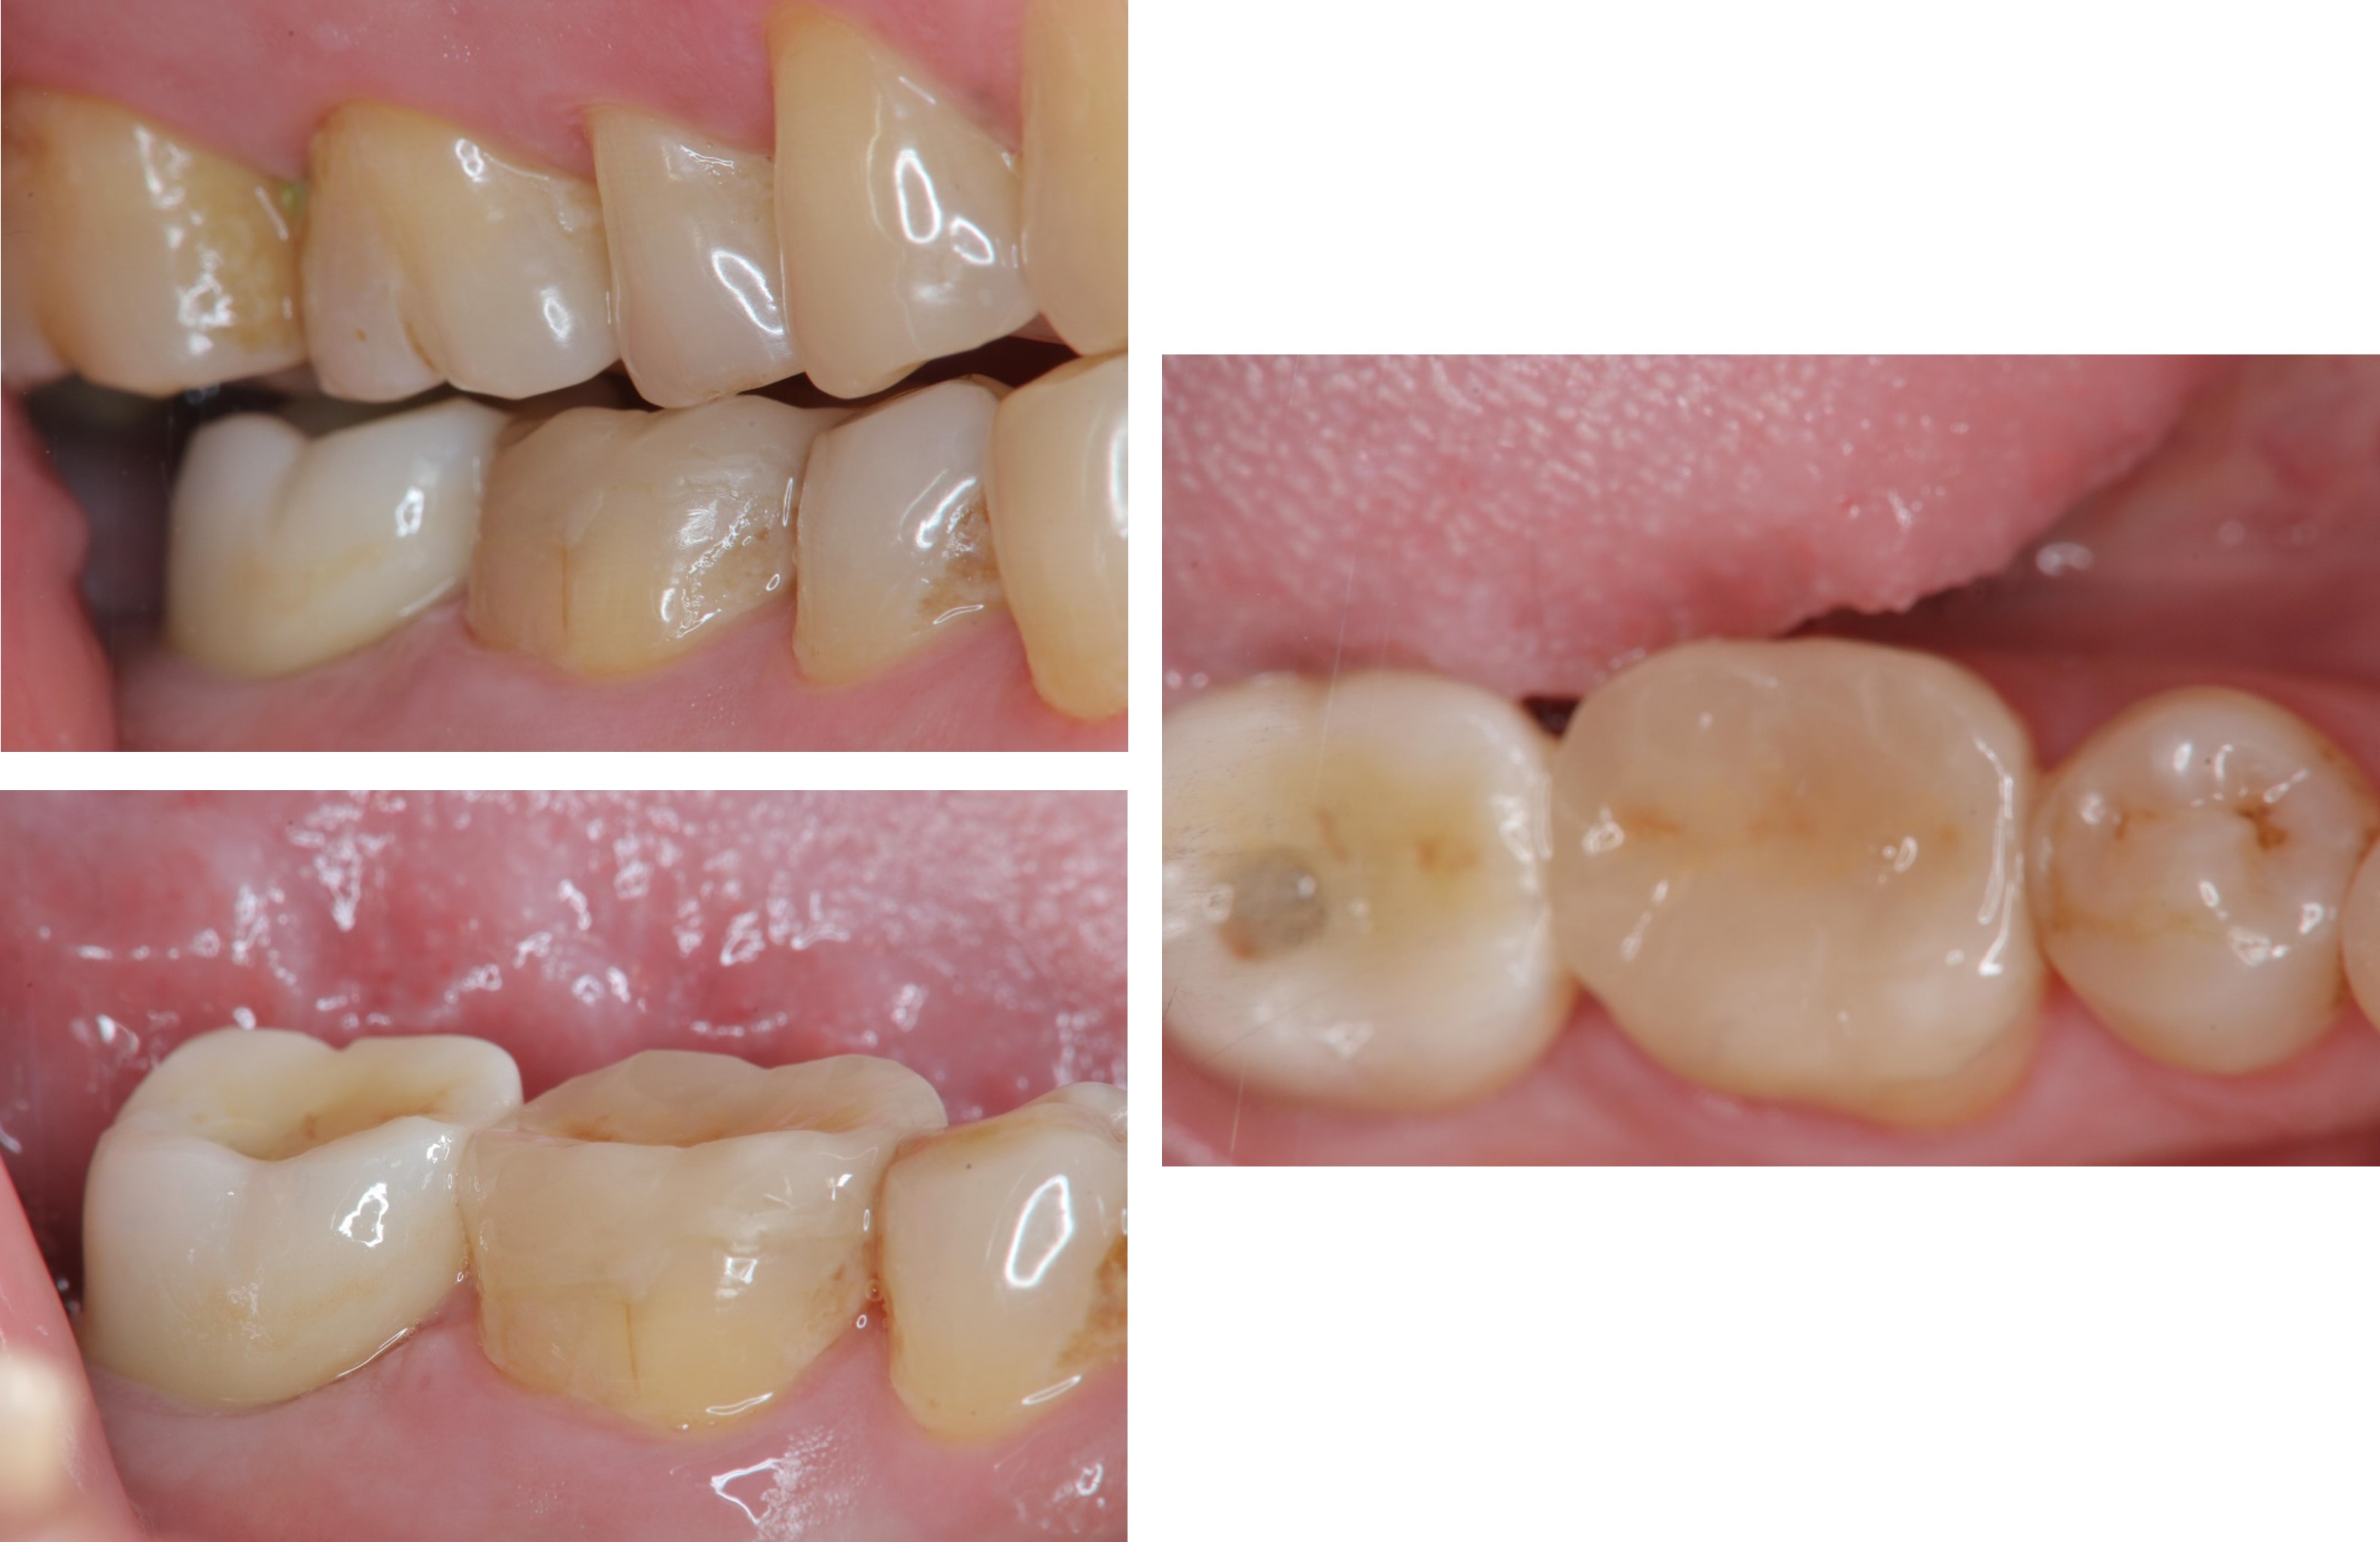

治療前,二次蛀牙,咬頭受損

蛀牙未到牙髓

冠塊體體製備

照相比色